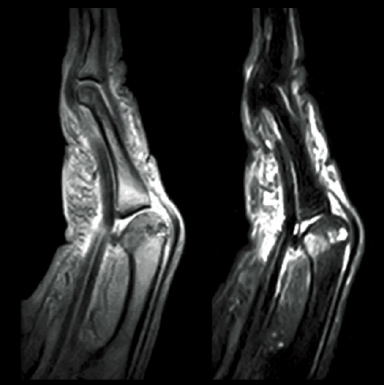

left:T2*WI right:STIR

T2*WI